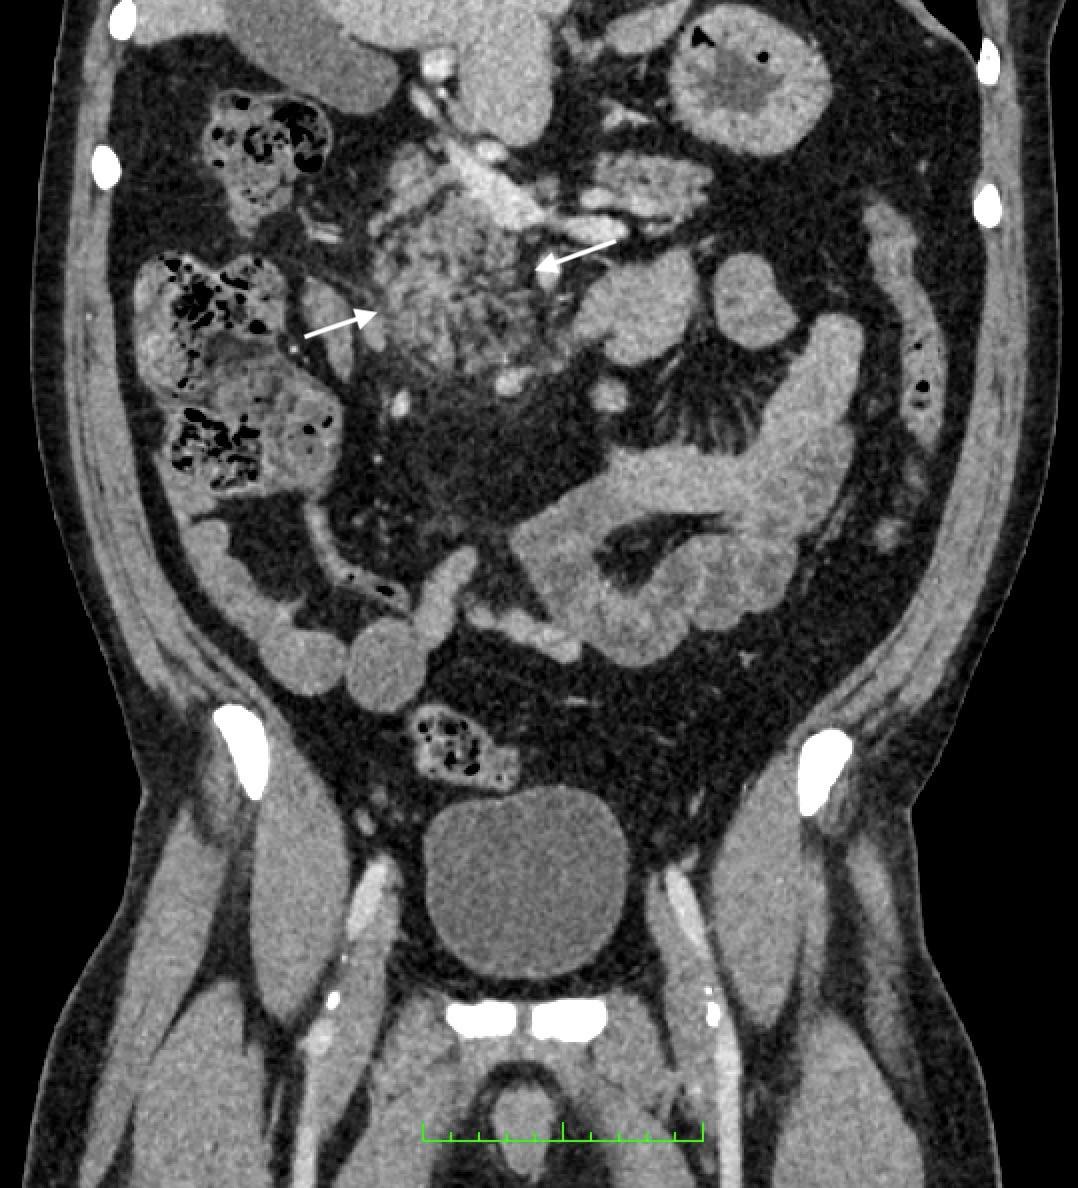

calculate bicarbonate and base excess due to a pH more than 7.70. The patient underwent an abdominal ultrasound in the ED, which suggested IHPS with an enlarged pyloric channel measuring 2.1 cm and a thickened muscle measuring 0.5 cm, again with minimal passage of fluids through the pylorus (Image 1). The surgical team was consulted for the abnormal laboratory and ultrasound findings, but due to the possibility of postoperative edema or residual abnormal external pylorus measurements, the consultant recommended further imaging to conclusively determine pyloric stenosis. The child was admitted for fluid resuscitation and electrolyte replacement. An upper GI series performed the same day confirmed the diagnosis of IHPS when there was lack of contrast passing from the stomach to the duodenum. The patient received a solution of intravenous 5%, dextrose, half normal saline, and 40 mEq potassium chloride at maintenance until electrolytes and intravascular volume